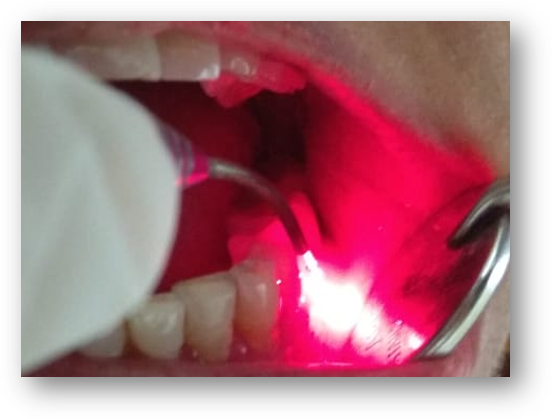

The purpose of initial periodontal treatment is to restore periodontal health. Pocket treatment begins in the area of deepest pocket depth and progresses to lesser involved areas. At GUMSOPOLIS we do debridement of hard deposits on the teeth and root surfaces by ultrasonic and hand instrumentation, followed by laser bacterial reduction and laser coagulation of the soft tissue of the surface, reducing inflammation.

Laser therapy for gum surgery has been used as an adjunct to scaling and root planing employed in the treatment of gum diseases.

Laser prevents epithelial downgrowth along the flap margin for up to 14 days longer than conventional gum surgeries. It also reduces inflammation due to decreased bacterial count.